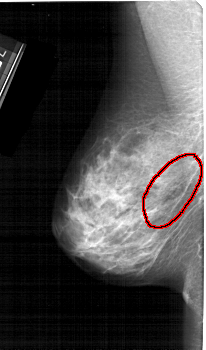

FILE: A_1391_1.LEFT_CC.OVERLAY

TOTAL_ABNORMALITIES 1

ABNORMALITY 1

LESION_TYPE CALCIFICATION TYPE PLEOMORPHIC DISTRIBUTION SEGMENTAL

ASSESSMENT 4

SUBTLETY 4

PATHOLOGY BENIGN

TOTAL_OUTLINES 1

BOUNDARY